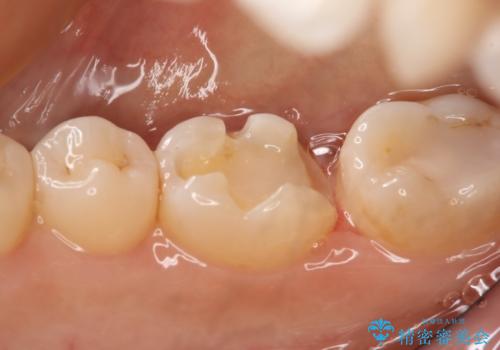

- 右下大臼歯の保険材料劣化に伴う虫歯の治療を希望された患者さまです。

審美性や精度の高い治療を希望されたので切削量や形態を考慮し、セラミックインレーでの治療を選択しました。

保険治療で使用される材料は劣化しやすく直下で虫歯が進行していることが多いです。

今回の患者さまは遠心部の虫歯が深かったのでCRで裏層した上で形成・印象を行いインレーセットを行っています。